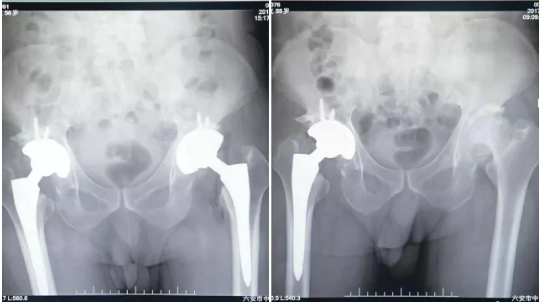

六安中山医院骨科送来了一面锦旗,患者刘先生,家住霍邱县夏店砖井村56岁,因“双侧髋关节疼痛伴活动受限10年”于17年10月份来到六安中山医院骨科,确诊为双侧股骨头无菌性坏死合并骨性关节炎,在吕建军教授带领的骨科团队下,进行了右侧全髋关节置换术,术后患者恢复良最好,特别满意,于11月24号再次进行左侧全髋关节置换术,目前患者已可以站立,行走,患者激动万分,不停地表示着对中山医师团队的感谢!

人工髋关节置换术主要用于治疗髋关节病变导致关节疼痛、功能障碍,包括退变性骨关节炎、股骨头坏死、髋关节发育不良、类风湿关节炎、强直性脊柱炎、股骨颈骨折等等。通过进行髋关节置换术,可以有效缓解关节疼痛、改善关节功能,并矫正畸形。再通过术后适当的锻炼,患者髋关节功能基本满足日常的生活需求,改善生活质量。